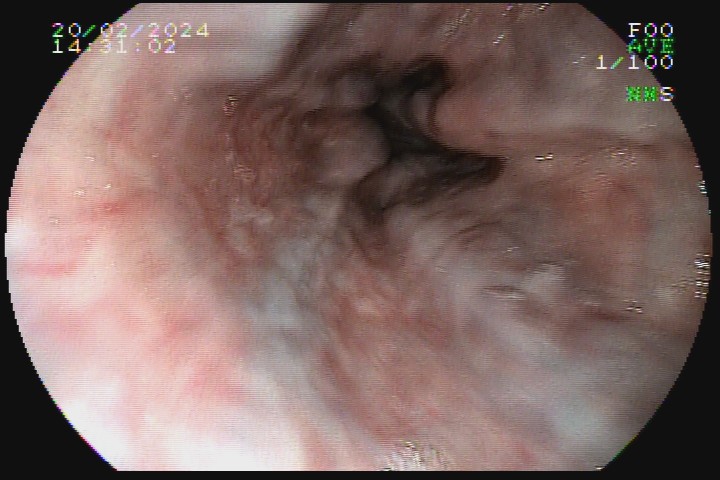

As varizes esofágicas devem ser classificadas em pequeno (<5mm), ou grosso calibre (>5mm), sendo esse o principal marcador prognóstico para o risco de sangramento e definição de conduta.

A presença de sinais da cor vermelha também é importante fator prognóstico. Eles surgem na superfície das varizes e são decorrentes da dilatação das vênulas superficiais, podendo ser em forma de vergão (red weal mark), de manchas cerejas (red spots) ou mancha hematocística.